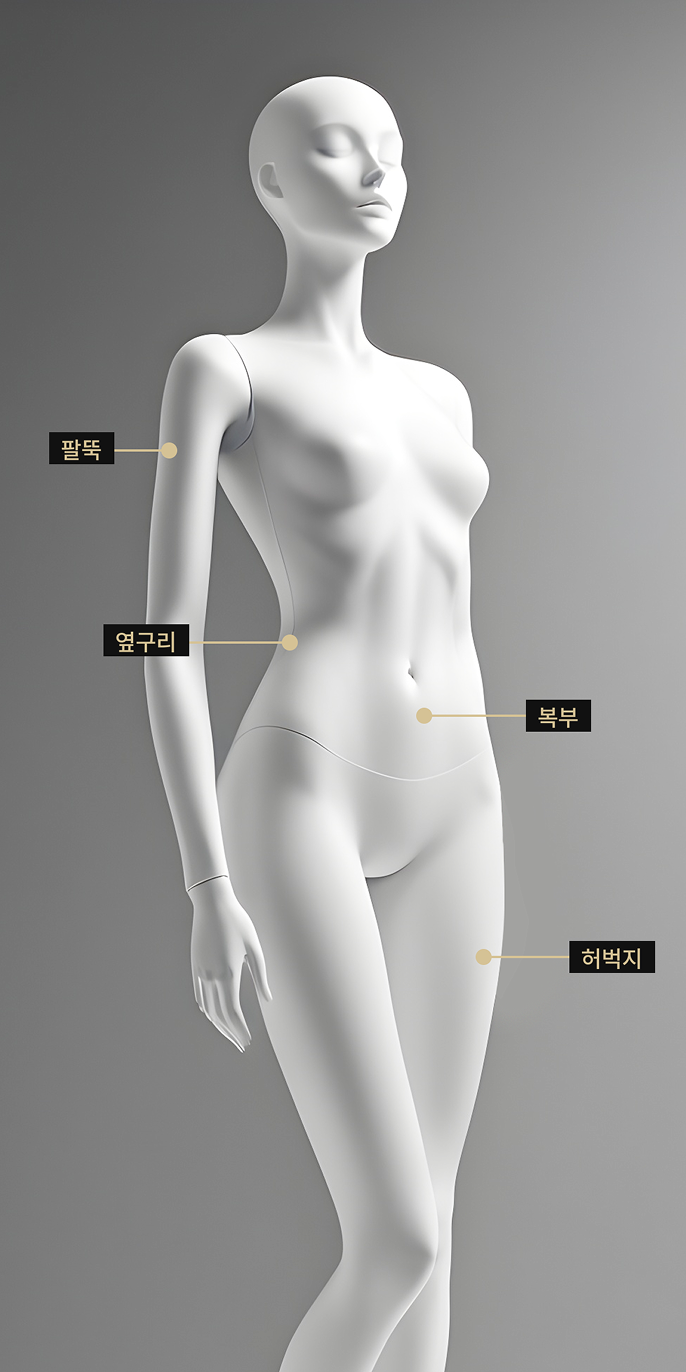

식이요법과 운동만으로는 둘레 감소가 어려운 팔뚝, 허벅지, 옆구리 등에

효과적입니다.

시술 부위

제로쏙 주사는 팔뚝, 허벅지, 옆구리 등

다이어트가 어려운 국소 부위에 추천드립니다.